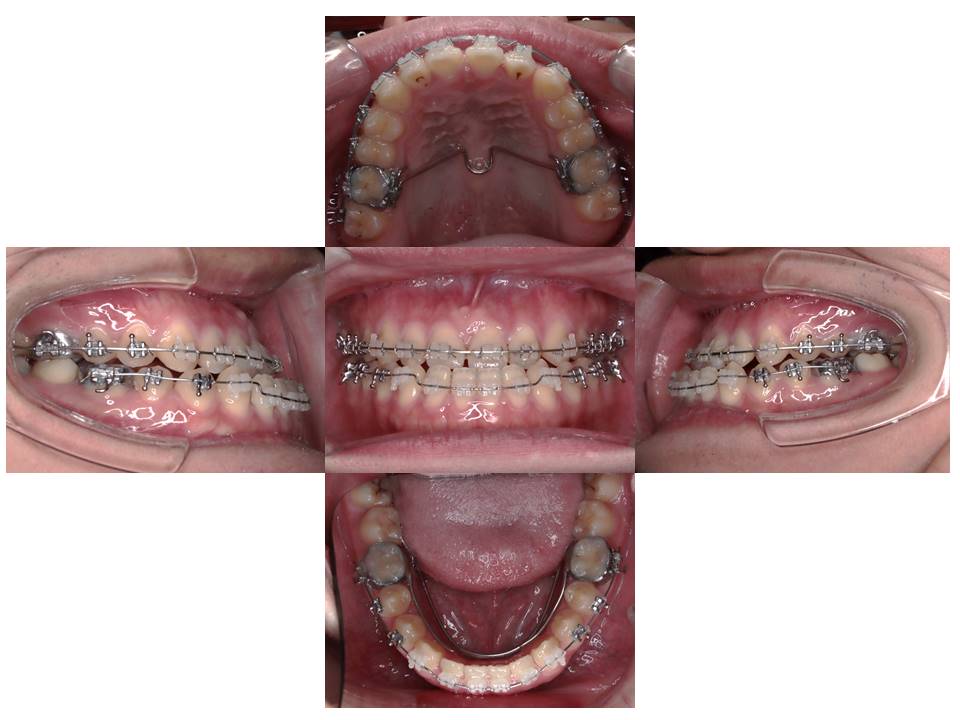

上下の歯列並べています